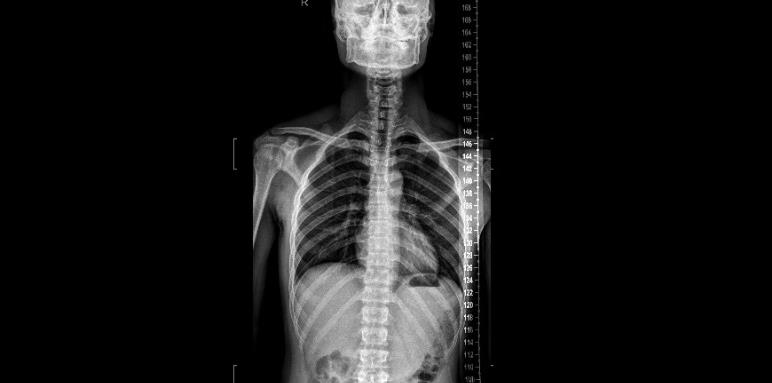

在解释上述问题的之前,我们先来直观的看一下MRI、CT、X线的图片。我找了一位发病经过最常见、求诊片子最凸显的病人做案例。来我科做手术的腰椎间盘突出症的患者多数为40-60岁年龄段(符合该病的发病年龄段)。

45岁女性患者,因“反复腰痛并左下肢疼痛3年余,再发并加重10余天”前来就诊的。

患者3年多以前,在无明显诱因的情况下出现腰痛,左下肢疼痛,以左大腿后侧明显,劳累时明显,久站久坐后加剧,休息后可以缓解。接受按摩等保守治疗(具体情况不详),效果一般。此后,上述症状反复发作。10多天以前,搬抬重物后再发并较前加重,伴有间歇性跛行。就诊于外院,接受腰椎间盘微创治疗(具体术式不详),疗效差。术后腰痛、左下肢疼痛未见明显缓解。近日,症状加重,出现左臀部疼痛、麻木,大便困难。为求进一步的治疗,前来我院。

X光片子